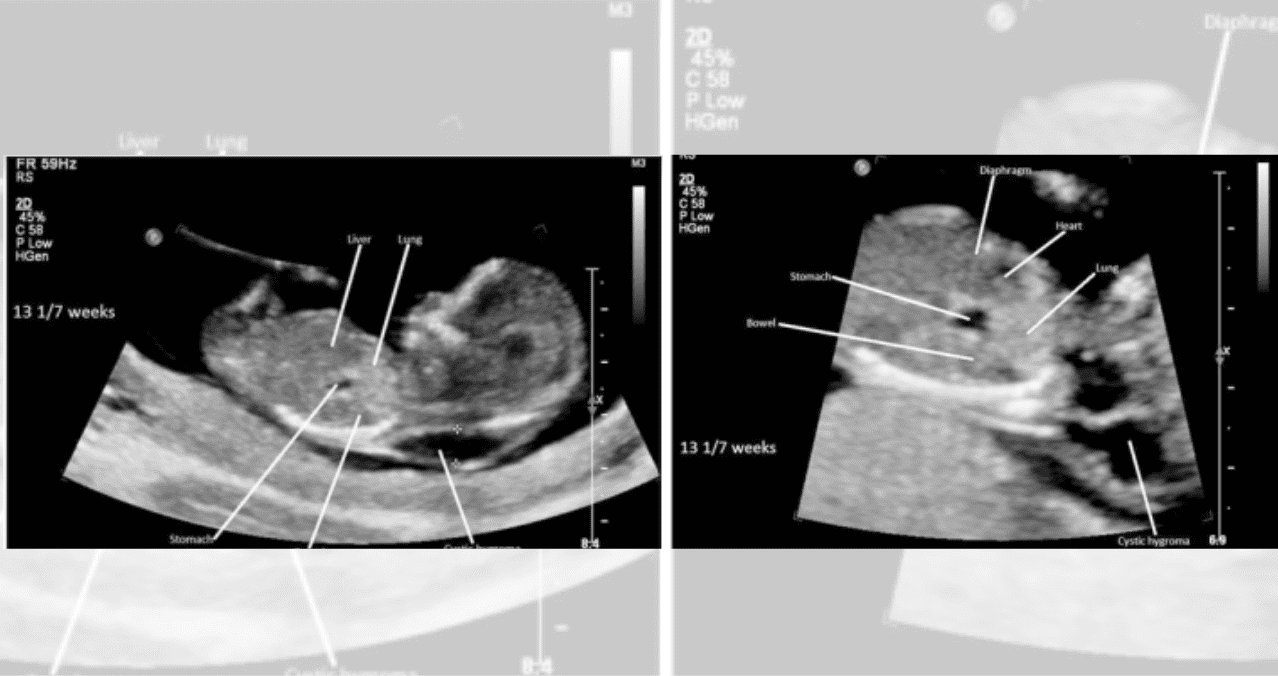

Large cystic hygroma (arrows). First trimester ultrasound (12 weeks),… Download Scientific

Hidrops fetal no inmune más higroma quístico en embarazada de 13 semanas de gestación. Reporte

Higroma quístico del primer trimestre Diagnóstico de hernia diafragmática congénita

Resolución espontánea del higroma quístico en un feto con síndrome de turner y evolución postnatal / Spontaneous resolution of cystichygroma in a fetus with turner syndrome and postnatal evolution. Results. The overall incidence of cystic hygroma was 1/1851 live newborns. The mean gestational age at diagnosis was 14.6 weeks and the mean maternal age at diagnosis was 29 years. Seventy percent of cystic hygromas had associated anomalies and 63% of the karyotypes studied were abnormal. Induced abortion was performed in 56%.